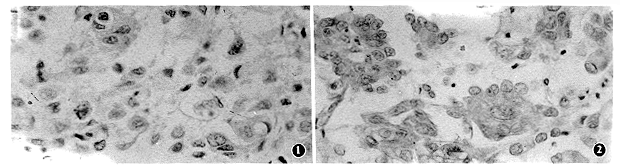

60例乳腺癌及乳腺各组织P-gp表达情况见附表。60例乳腺癌组织29例阳性,占48.3%。癌组织内黄棕色颗粒样着色,呈簇状或散在性分布于细胞浆及细胞膜上,不同组织间及同一组织的不同瘤灶内染色强度及分布不均(图1,2)。癌旁乳腺小叶增生组织内有程度不同的阳性表达,且分布不均;而癌旁正常组织无阳性表达。正常乳腺组织中可见散在的少数细胞染色。ER(+)46例,ER(-)14例;PR(+)16例,PR(-)44例。乳腺癌P-gp表达与年龄、

本组资料表明,乳腺正常组织无P-gp阳性表达,乳腺增生病及纤维腺瘤呈弱阳性表达,乳腺癌旁增生组织有程度不同的弱阳性表达,乳腺癌有较高水平表达。乳腺组织在向癌的演变过程中,是否因为MDR1基因被激活致使P-gp表达水平增高,尚未见相关报道,有待继续研究。本组乳腺癌组织P-gp阳性率与文献报道[2,3]结果相近。我们观察到在不同病理组织类型中、或相同组织类型、或同一切片的不同瘤灶内可看到分布及染色强度不均一,这一特点可能与乳腺癌组织异质性有关,也是乳腺癌化疗疗效个体差异及肿块不均匀缩小的原因之一。